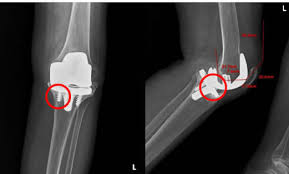

무릎 인공관절 수술, 왜 필요한가요?

무릎관절은 체중을 가장 많이 지탱하는 관절입니다. 나이가 들수록 연골은 점차 마모되고, 충격을 흡수하는 능력도 감소합니다. 이로 인해 통증, 뻣뻣함, 운동 제한이 생기며, 이런 증상이 악화되면 인공관절 수술이 필요해집니다.

퇴행성 관절염 외에도 류마티스 관절염이나 외상 후 관절 손상이 심각할 경우 수술이 권유되며, 수술을 통해 환자는 통증 없이 보행이 가능해지고 일상생활로 복귀할 수 있게 됩니다.